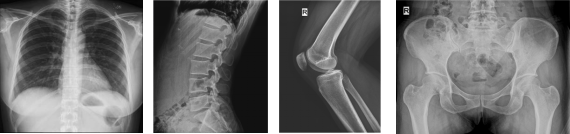

由于不同的患者可能进行投照的部位不同,这就要求科室使用的设备必须完全满足所有可能出现部位的投照需求。同时为保护患者和医生,避免可能出现的医疗风险,设备的使用和操作也必须符合常规的工作流程。悬吊式双移动平板DR,能全面覆盖立位、卧位、斜位、轴位以及轮椅、担架位等各种体位投照;外观精美大气,完全满足放射科日常工作使用需求。